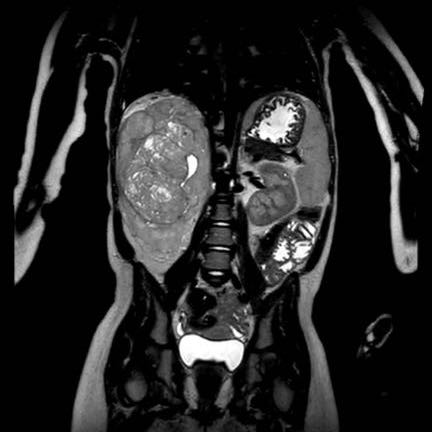

Ca lâm sàng 1

Hình ảnh chuỗi xung T2W mặt phẳng coronal cho thấy một khối u không đồng nhất ở thận trái với các thành phần nang nhỏ.

Khối u ngấm thuốc kém hơn so với phần nhu mô thận bình thường còn lại ở ngoại vi.

Các thành phần đặc của khối u cho thấy hạn chế khuếch tán rõ rệt (mũi tên).

Đây là u Wilms ở bé trai năm tuổi. Hóa trị tiền phẫu được thực hiện theo phác đồ Umbrella của SIOP-RTSG, sau đó tiến hành cắt thận.